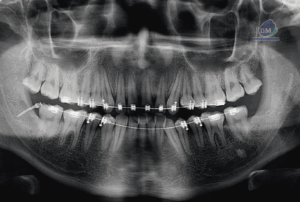

CORTES AXIALES

CORTES TRANSAXIALES

CORTES TANGENCIALES